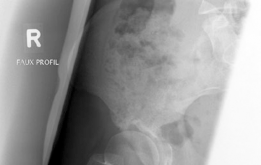

Beyond the AP pelvis, the False Profile view of Lequesne and de Sèze is mandatory to evaluate anterior coverage, which is frequently deficient in DDH. This view allows for the measurement of the Anterior Center Edge Angle (ACEA). In this patient, the ACEA is markedly reduced, correlating directly with her positive anterior apprehension test and the anterior location of her labral tear. We must also scrutinize the AP radiograph for signs of acetabular retroversion, such as the crossover sign, ischial spine sign, and posterior wall sign. Dysplasia is rarely a simple lack of lateral coverage; it is often a complex, multi-planar deformity where the acetabulum is not only shallow but also maloriented in the sagittal and axial planes.

With the acetabular fragment now mobile, a 5.0mm Schanz pin is placed into the supra-acetabular region to act as a joystick. The fragment is mobilized and rotated laterally and anteriorly to achieve the pre-planned coverage. We also intentionally medialize the fragment to optimize the abductor lever arm. The hip is taken through a full range of motion to ensure there is no iatrogenic anterior impingement. Fluoroscopy is utilized extensively at this stage. We obtain AP, false profile, and obturator oblique views to confirm the correction of the LCEA, ACEA, and Shenton's line, and to ensure the joint space remains perfectly congruent.